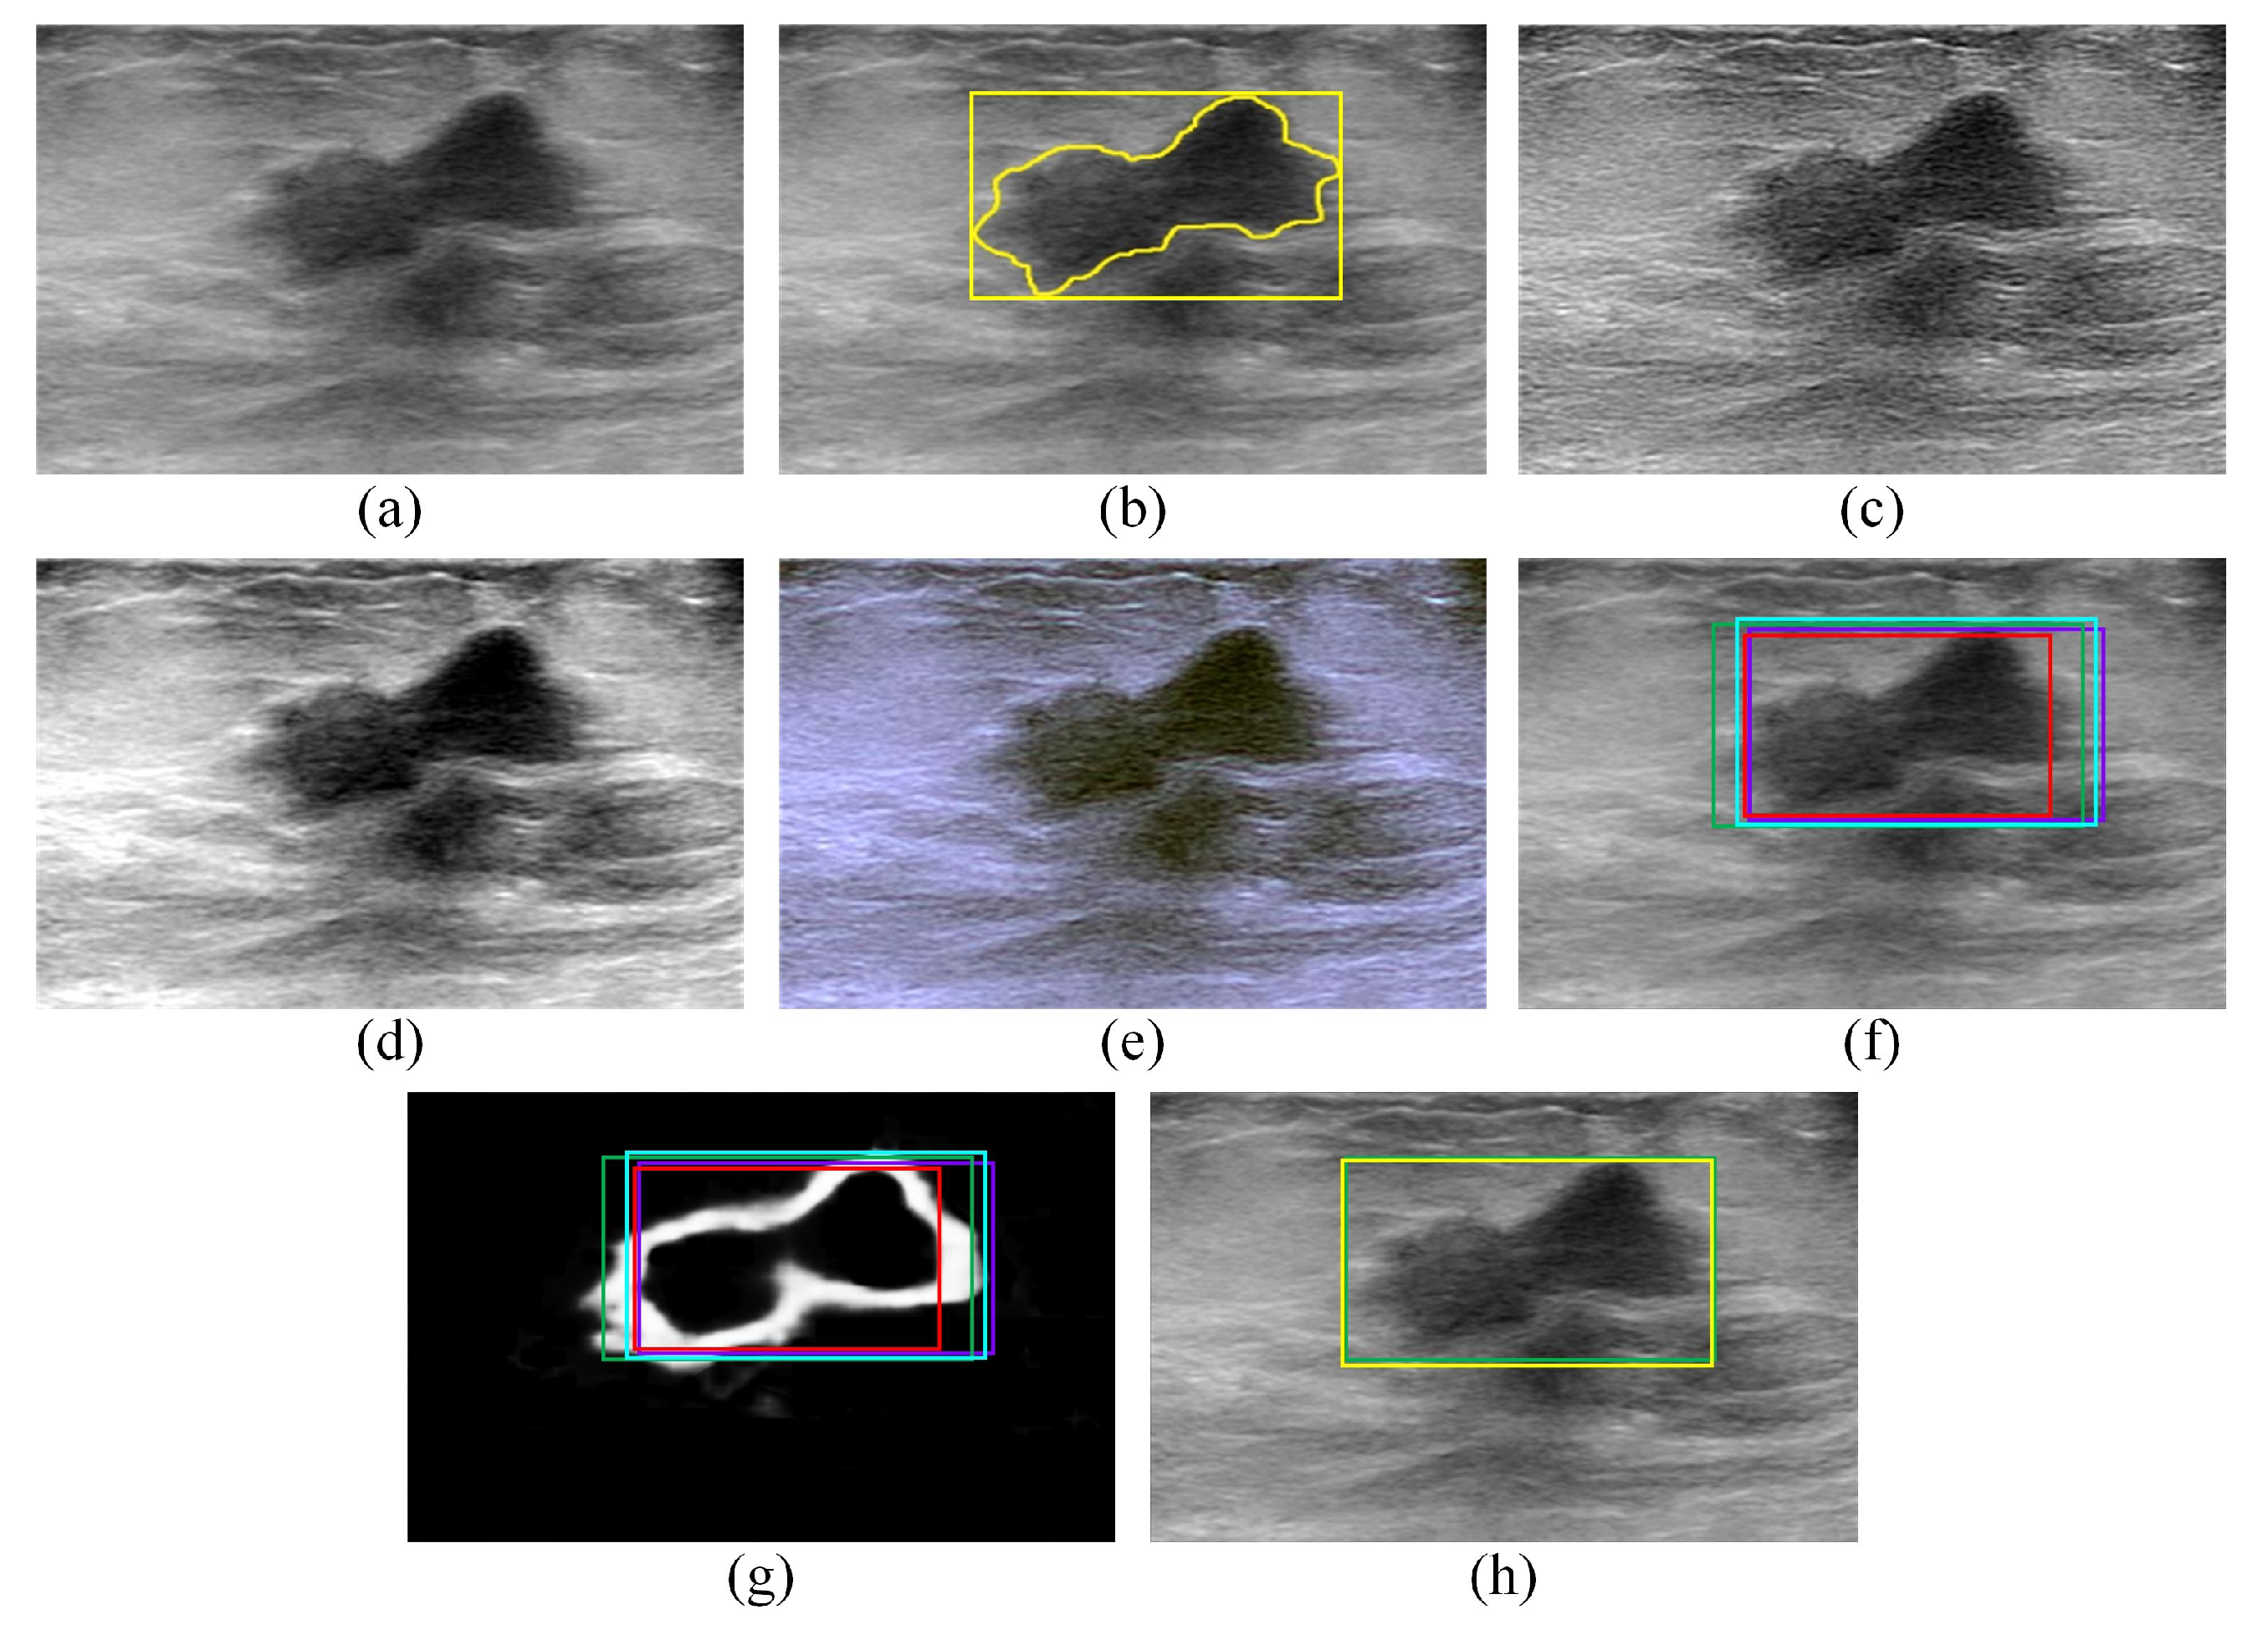

The edge map computed for a given BUS image using the DexiNed model can be used to analyze ROIs generated for that BUS image using different deep learning object-detection models. For example, consider the BUS image presented in Figure 1a. The gold standard tumor outline (yellow outline) and the gold standard ROI (yellow box) are shown in Figure 1b. The gold standard tumor outline is obtained by asking a radiologist (fourth author) with 15 years of experience in BUS imaging to segment tumor three times. The mean of the three manual segmentations is taken as the gold standard tumor outline. Furthermore, the gold standard ROI is taken as the smallest rectangular bounding box that contains the gold standard tumor outline. This approach for identifying the gold standard ROI has been employed in many previous studies, such as [18,30]. The edge map computed for the BUS image using the DexiNed model is presented in Figure 1c. Figure 1d,e show three hypothetical ROIs overlaid on the BUS image and the edge map, respectively. The first ROI, which is called ROI 1, covers a sub-region of the gold standard ROI and its area is smaller than the gold standard ROI by . The second ROI, which is called ROI 2, covers the gold standard ROI, but its area is larger than the gold standard ROI by . The third ROI, which is called ROI 3, covers the gold standard ROI, but its area is larger than the gold standard ROI by . Hence, ROI 2 provides an improved localization of the region that contains the tumor compared to ROI 1 and ROI 3. Each one of the three hypothetical ROIs can be analyzed to select the ROI that provides an improved localization of the region that contains tumors.

Figure 1.

(a,b) (a) A malignant BUS image and (b) the corresponding gold standard tumor outline (yellow outline) and gold standard ROI (yellow box) that contains the tumor. (c) The edge map computed using the DexiNed model. (d–f) Three hypothetical ROIs (ROI 1, ROI 2, and ROI 3) overlaid on (d) the BUS image, (e) the edge map, and (f) the binarized edge map.

where is the value of the binarized edge map at the pixel with coordinates , N is the width of the ROI measured in pixels, and M is the height of the ROI measured in pixels. Hence, the value of D decreases when the ROI includes a large number of false-positive pixels. In fact, the false-positive pixels represent pixels that are located within the ROI generated by the deep learning object-detection model but that are not included in the gold standard ROI. For example, Figure 1f shows the binarized edge map computed for the edge map presented in Figure 1c along with three hypothetical ROIs. The values of D computed for ROI 1, ROI 2, and ROI 3 are equal to 0.25, 0.26, and 0.18, respectively. Therefore, the D indicator provides an effective metric for differentiating between ROI 2 and ROI 3, where both ROIs have close S values, but they are different in terms of the number of false-positive pixels.

The two indicators, S and D, are combined to obtain a single metric, , that can be used to select the ROI that improves the localization of the region that contains the tumor. In particular, the ROI with the highest value is selected since it maximizes the number of true-positive pixels and minimizes the number of false-positive pixels that are included within the selected ROI. For example, in Figure 1f, the values computed for ROI 1, ROI 2, and ROI 3 are equal to 1377, 3298, and 2300, respectively. Therefore, ROI 2 is selected as the ROI that improves the localization of the region that contains the tumor.

For instance, consider the malignant BUS image presented in Figure 4a, which is the same BUS image shown in Figure 1a. The gold standard tumor outline (yellow outline) and the gold standard ROI (yellow box) are presented in Figure 4b. Figure 4c,d show the sharpened image and contrast-enhanced image, respectively, that are computed for the BUS image in Figure 4a. Moreover, Figure 4e shows the artificial RGB image that is constructed by concatenating the BUS image, the sharpened image, and the contrast-enhanced image.

Figure 4.

(a,b), the (a) A malignant BUS image and (b) the corresponding gold standard tumor outline (yellow outline) and gold standard ROI (yellow box) that contains the tumor. (c–e) The (c) sharpened image, (d) contrast-enhanced image, and (e) artificial RGB image computed for the B-mode image presented in (a). (f) The ROI localizations generated by the Faster R-CNN (violet box), SSD (red box), EfficientDet-D0 (cyan box), and CenterNet (green box) models overlaid on the BUS image. (g) The ROI localizations generated by the Faster R-CNN (violet box), SSD (red box), EfficientDet-D0 (cyan box), and CenterNet (green box) models overlaid on the edge map. (h) The ROI selected by the proposed edge-based selection method (in this case, the ROI generated by the CenterNet model—green box) as well as the gold standard tumor outline (yellow box) overlaid on the BUS image.

The proposed edge-based selection method is used to process the four ROIs generated by the Faster R-CNN, SSD, EfficientDet-D0, and CenterNet models with the goal of selecting the ROI that improves the localization of the region that contains the tumor in the BUS image. For example, consider the ROIs in Figure 4f,g that are generated by the Faster R-CNN (violet box), SSD (red box), EfficientDet-D0 (cyan box), and CenterNet (green box) models. The values computed for the ROIs generated by the Faster R-CNN, SSD, EfficientDet-D0, and CenterNet models are equal to 2732, 2328, 3173, and 3605, respectively. The value calculated for the ROI generated by the CenterNet model is higher than the values computed for the ROIs generated by the three other models. Therefore, the ROI generated by the CenterNet model (green box) is selected by the proposed edge-based selection method, as shown in Figure 4h. To facilitate the comparison between the ROI selected by the proposed edge-based selection method and the gold standard ROI, Figure 4h also presents the gold standard ROI (yellow box).